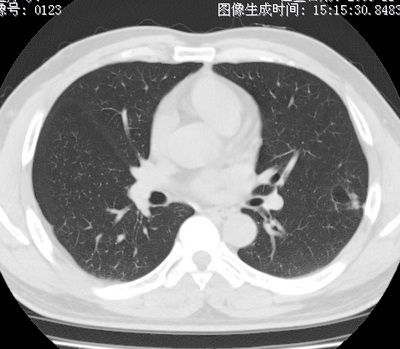

以下是引用zhao_bin2008在2010-1-4 20:15:00的发言:[br]先天性肺囊肿或小的肺隔离症?

以下是引用卜一在2010-1-4 22:09:00的发言:[br]先天性肺囊肿或小的肺隔离症?支持!

以下是引用zsl6918在2010-1-5 5:23:00的发言:[br]良性改变!肺囊肿,先天性支气管闭锁,血管畸形等均有可能。

以下是引用影像之路在2010-1-6 11:10:00的发言:[br]腺癌,最终的病检有些出乎意料之外,术前同志们大多考虑为肺囊肿或小的肺隔离征 [br]回过头来看 小结节呈分叶状,其内侧有一条较粗的静脉供血或许能成为支持诊断腺癌的理由